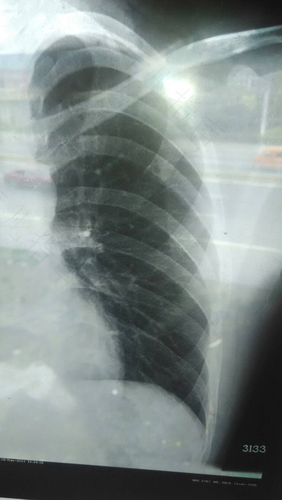

很多因素会引起胸闷现象,冠心病,心肌供血不足,肺气肿,肺心病,因此要到医院进行检查胸片,做心电图,排除心脏疾病。也有可能是因为精神因素导致,平时一定要注意自己的生活方式,调解心情不要过度劳累,按照医生的嘱咐用药。